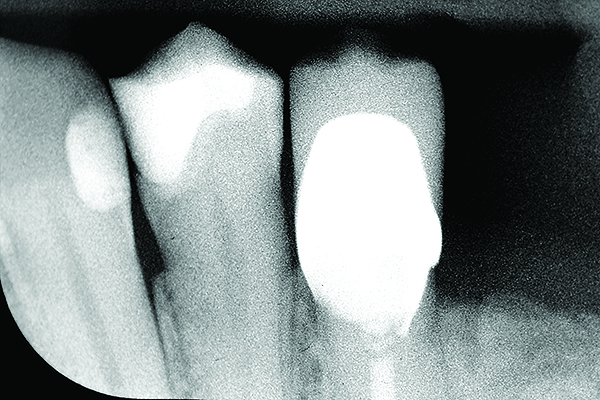

Layered Zirconia Crown / It is hard to spot a zirconia crown amongst natural teeth.